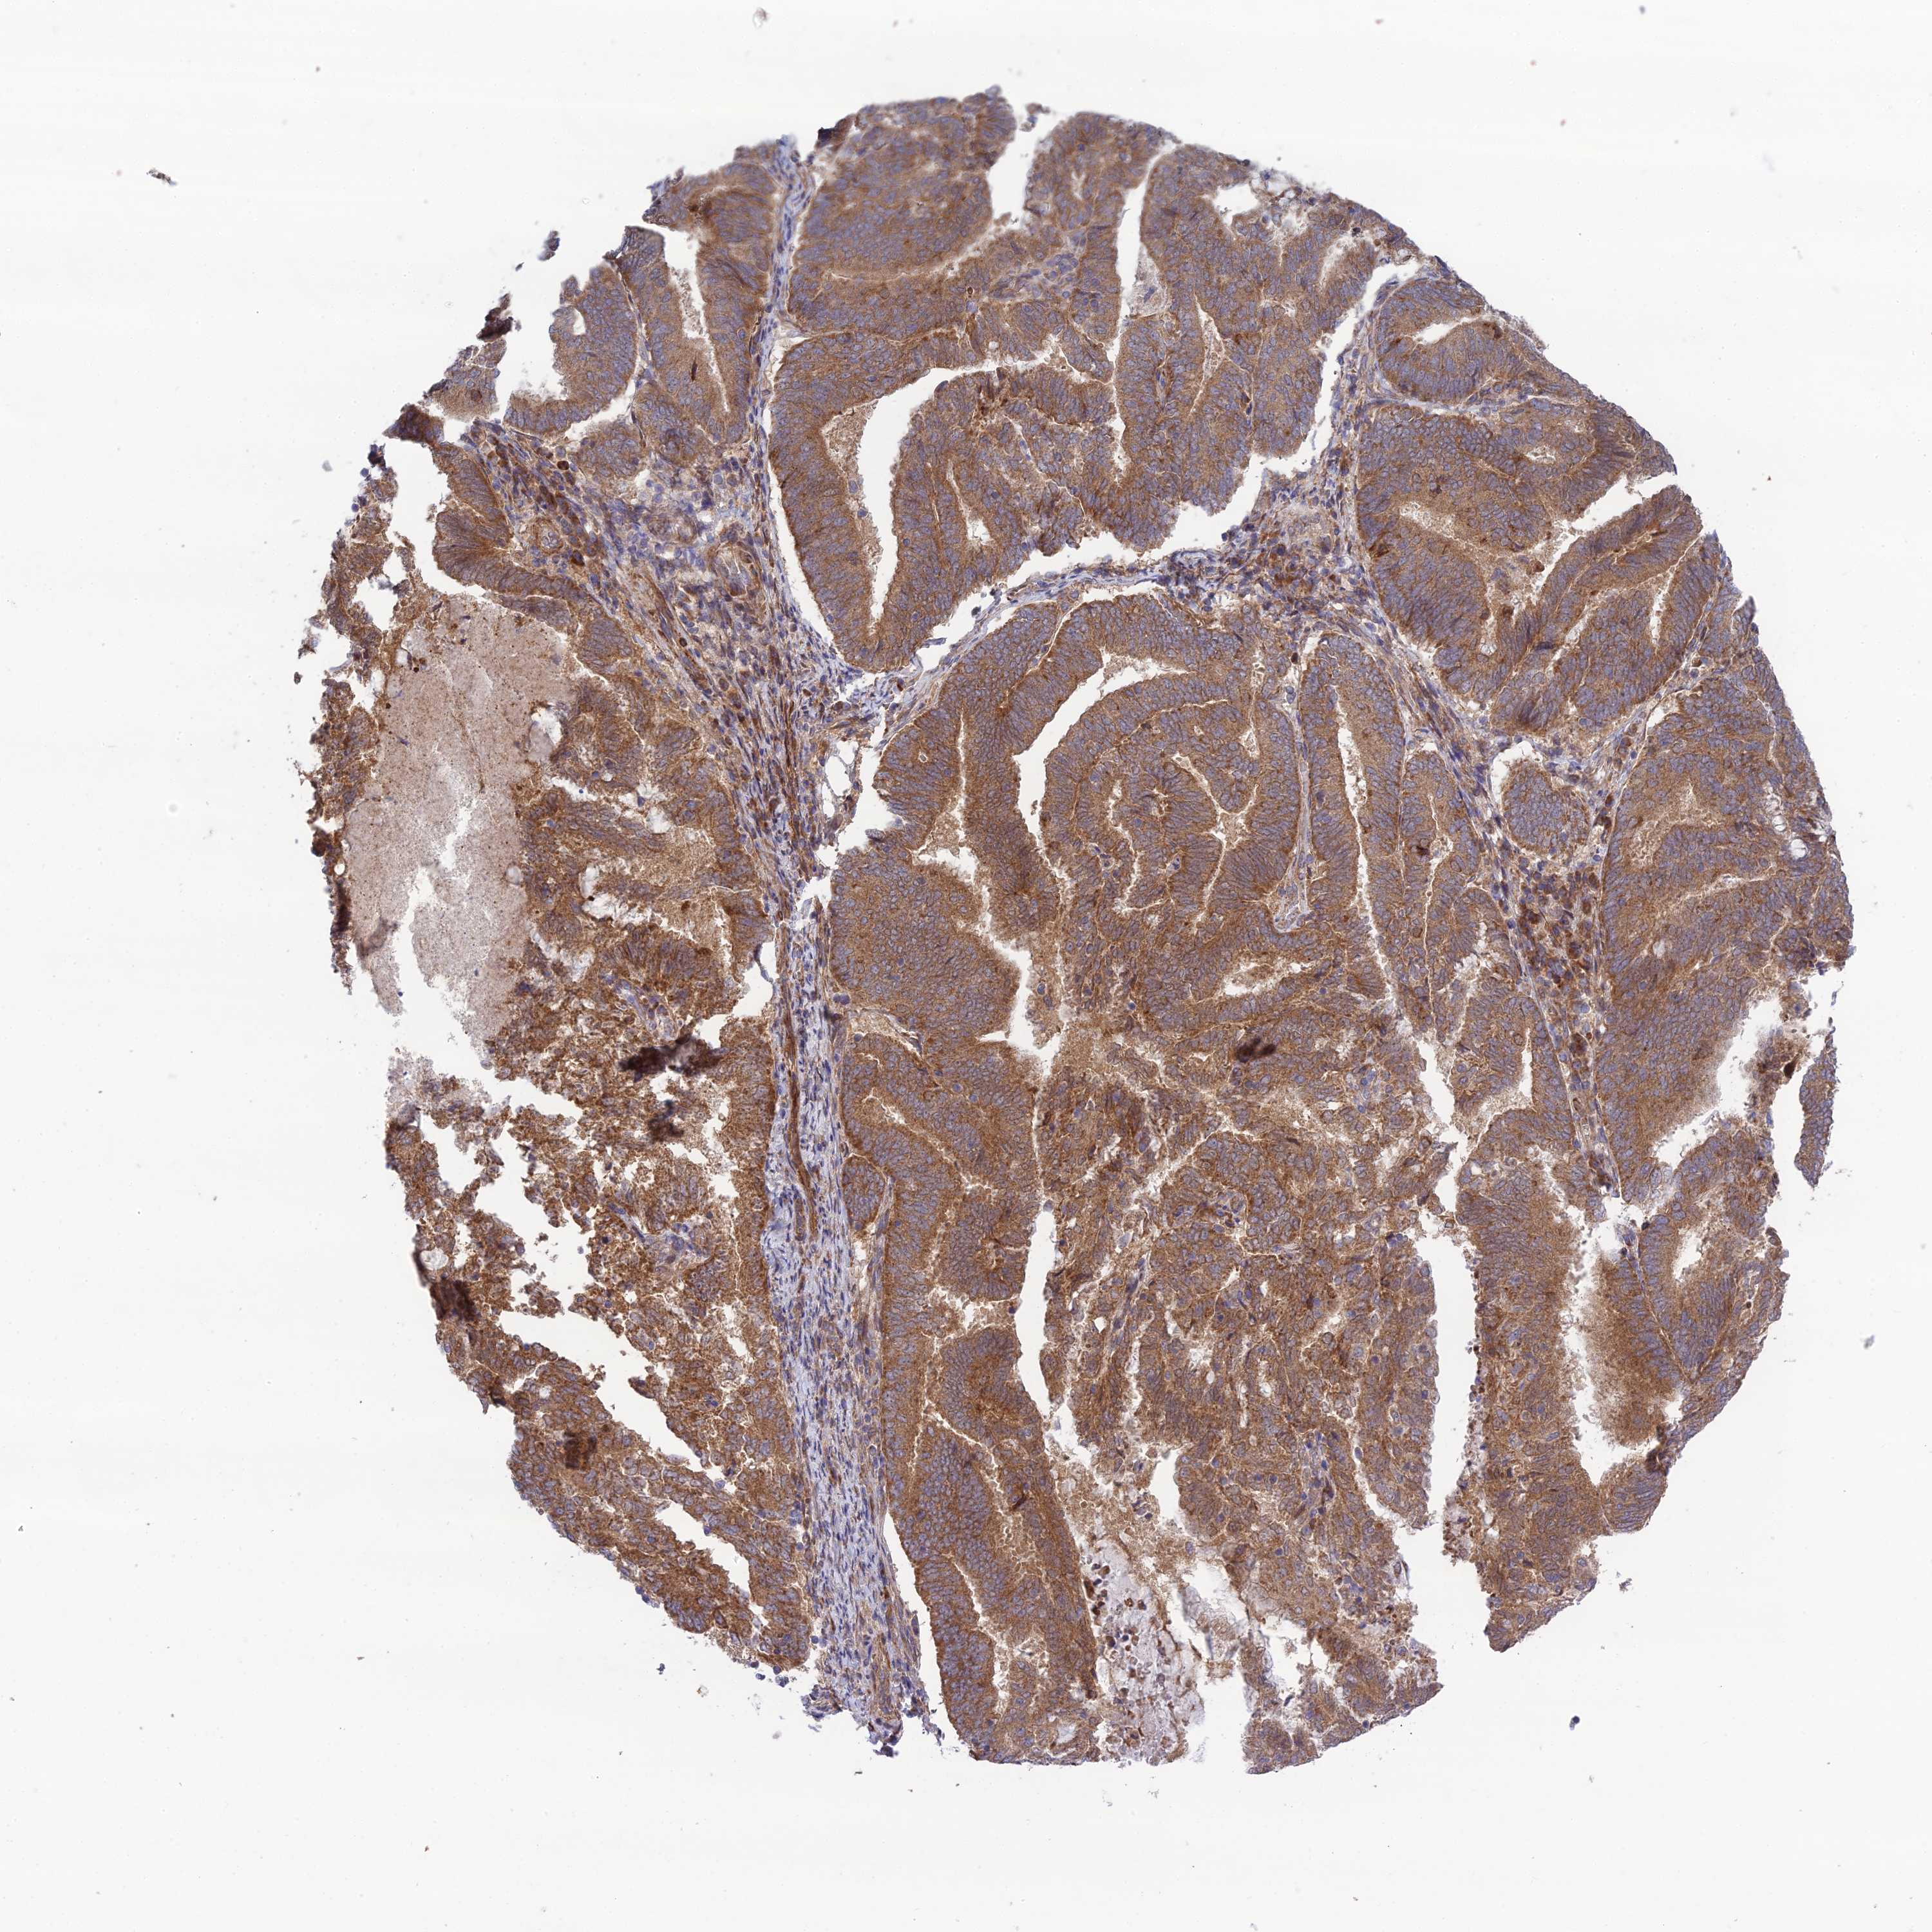

ENDOMETRIAL CANCER - Protein expressioni

A mouse-over function shows sample information and annotation data. Click on an image to view it in a full screen mode. Samples can be filtered based on level of antibody staining by selecting one or several of the following categories: high, medium, low and not detected. The assay and annotation is described here.

Note that samples used for immunohistochemistry by the Human Protein Atlas do not correspond to samples in the TCGA dataset.

Antibody stainingi

Antibody staining in the annotated cell types in the current human tissue is reported as not detected, low, medium, or high, based on conventional immunohistochemistry profiling in selected tissues. This score is based on the combination of the staining intensity and fraction of stained cells.

Each image is clickable and will lead to virtual microscopy that enables deeper exploration of all samples and also displays staining intensity scores, fraction scores and subcellular localization as well as patient and tissue information for each sample.

Antibody HPA044359

Staining

High

Medium

Low

Not detected

Intensity

Strong

Moderate

Weak

Negative

Quantity

>75%

75%-25%

<25%

None

Location

Nuclear

Cytoplasmic/membranous

Cytoplasmic/membranous,nuclear

Adenocarcinoma, NOS

Adenocarcinoma, metastatic, NOS